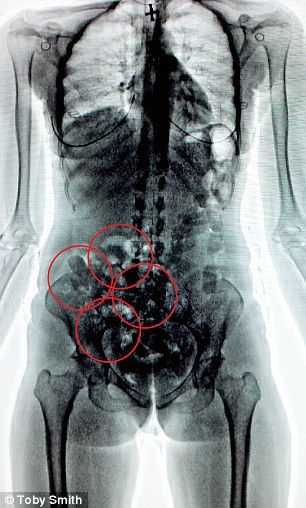

Теперь давайте сравним это с медицинским рентгеном. Когда врач отправляет вас на рентген, вы подвергаетесь воздействию гораздо более мощного излучения. Оно проникает глубоко в ткани, позволяя увидеть кости и внутренние органы. Это как если бы вместо душа вы оказались под мощным водопадом — эффект куда более сильный, не правда ли?